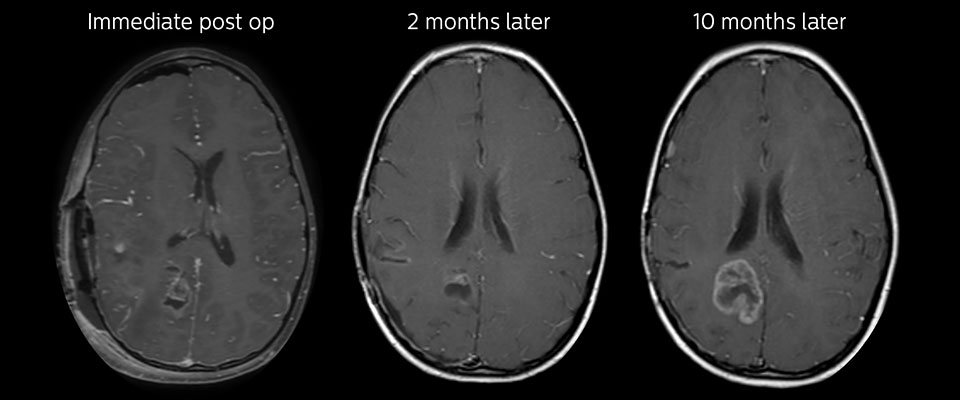

APT in post-surgery evaluation

Large metastatic brain lesion

This 10-year-old patient underwent Ewing’s sarcoma tumor resection 7 years ago, but was found to now have a large metastatic lesion in the brain. This lesion shows clearly increased APT signal.

MRI with APT post resection

Immediately post resection MRI was again performed. T2-weighted and postcontrast T1-weighted images are quite inconclusive for distinguishing residual tumor tissue from postoperative tissue changes. On the APT image some high signal is still seen, which would suggest residual tumor tissue.

Follow-up over time results

Follow-up over time

In later follow-up scans the post-contrast T1-weighted images suggest recurrent tumor growth. So, it would be interesting to study the predictive value of APT in a large patient group.